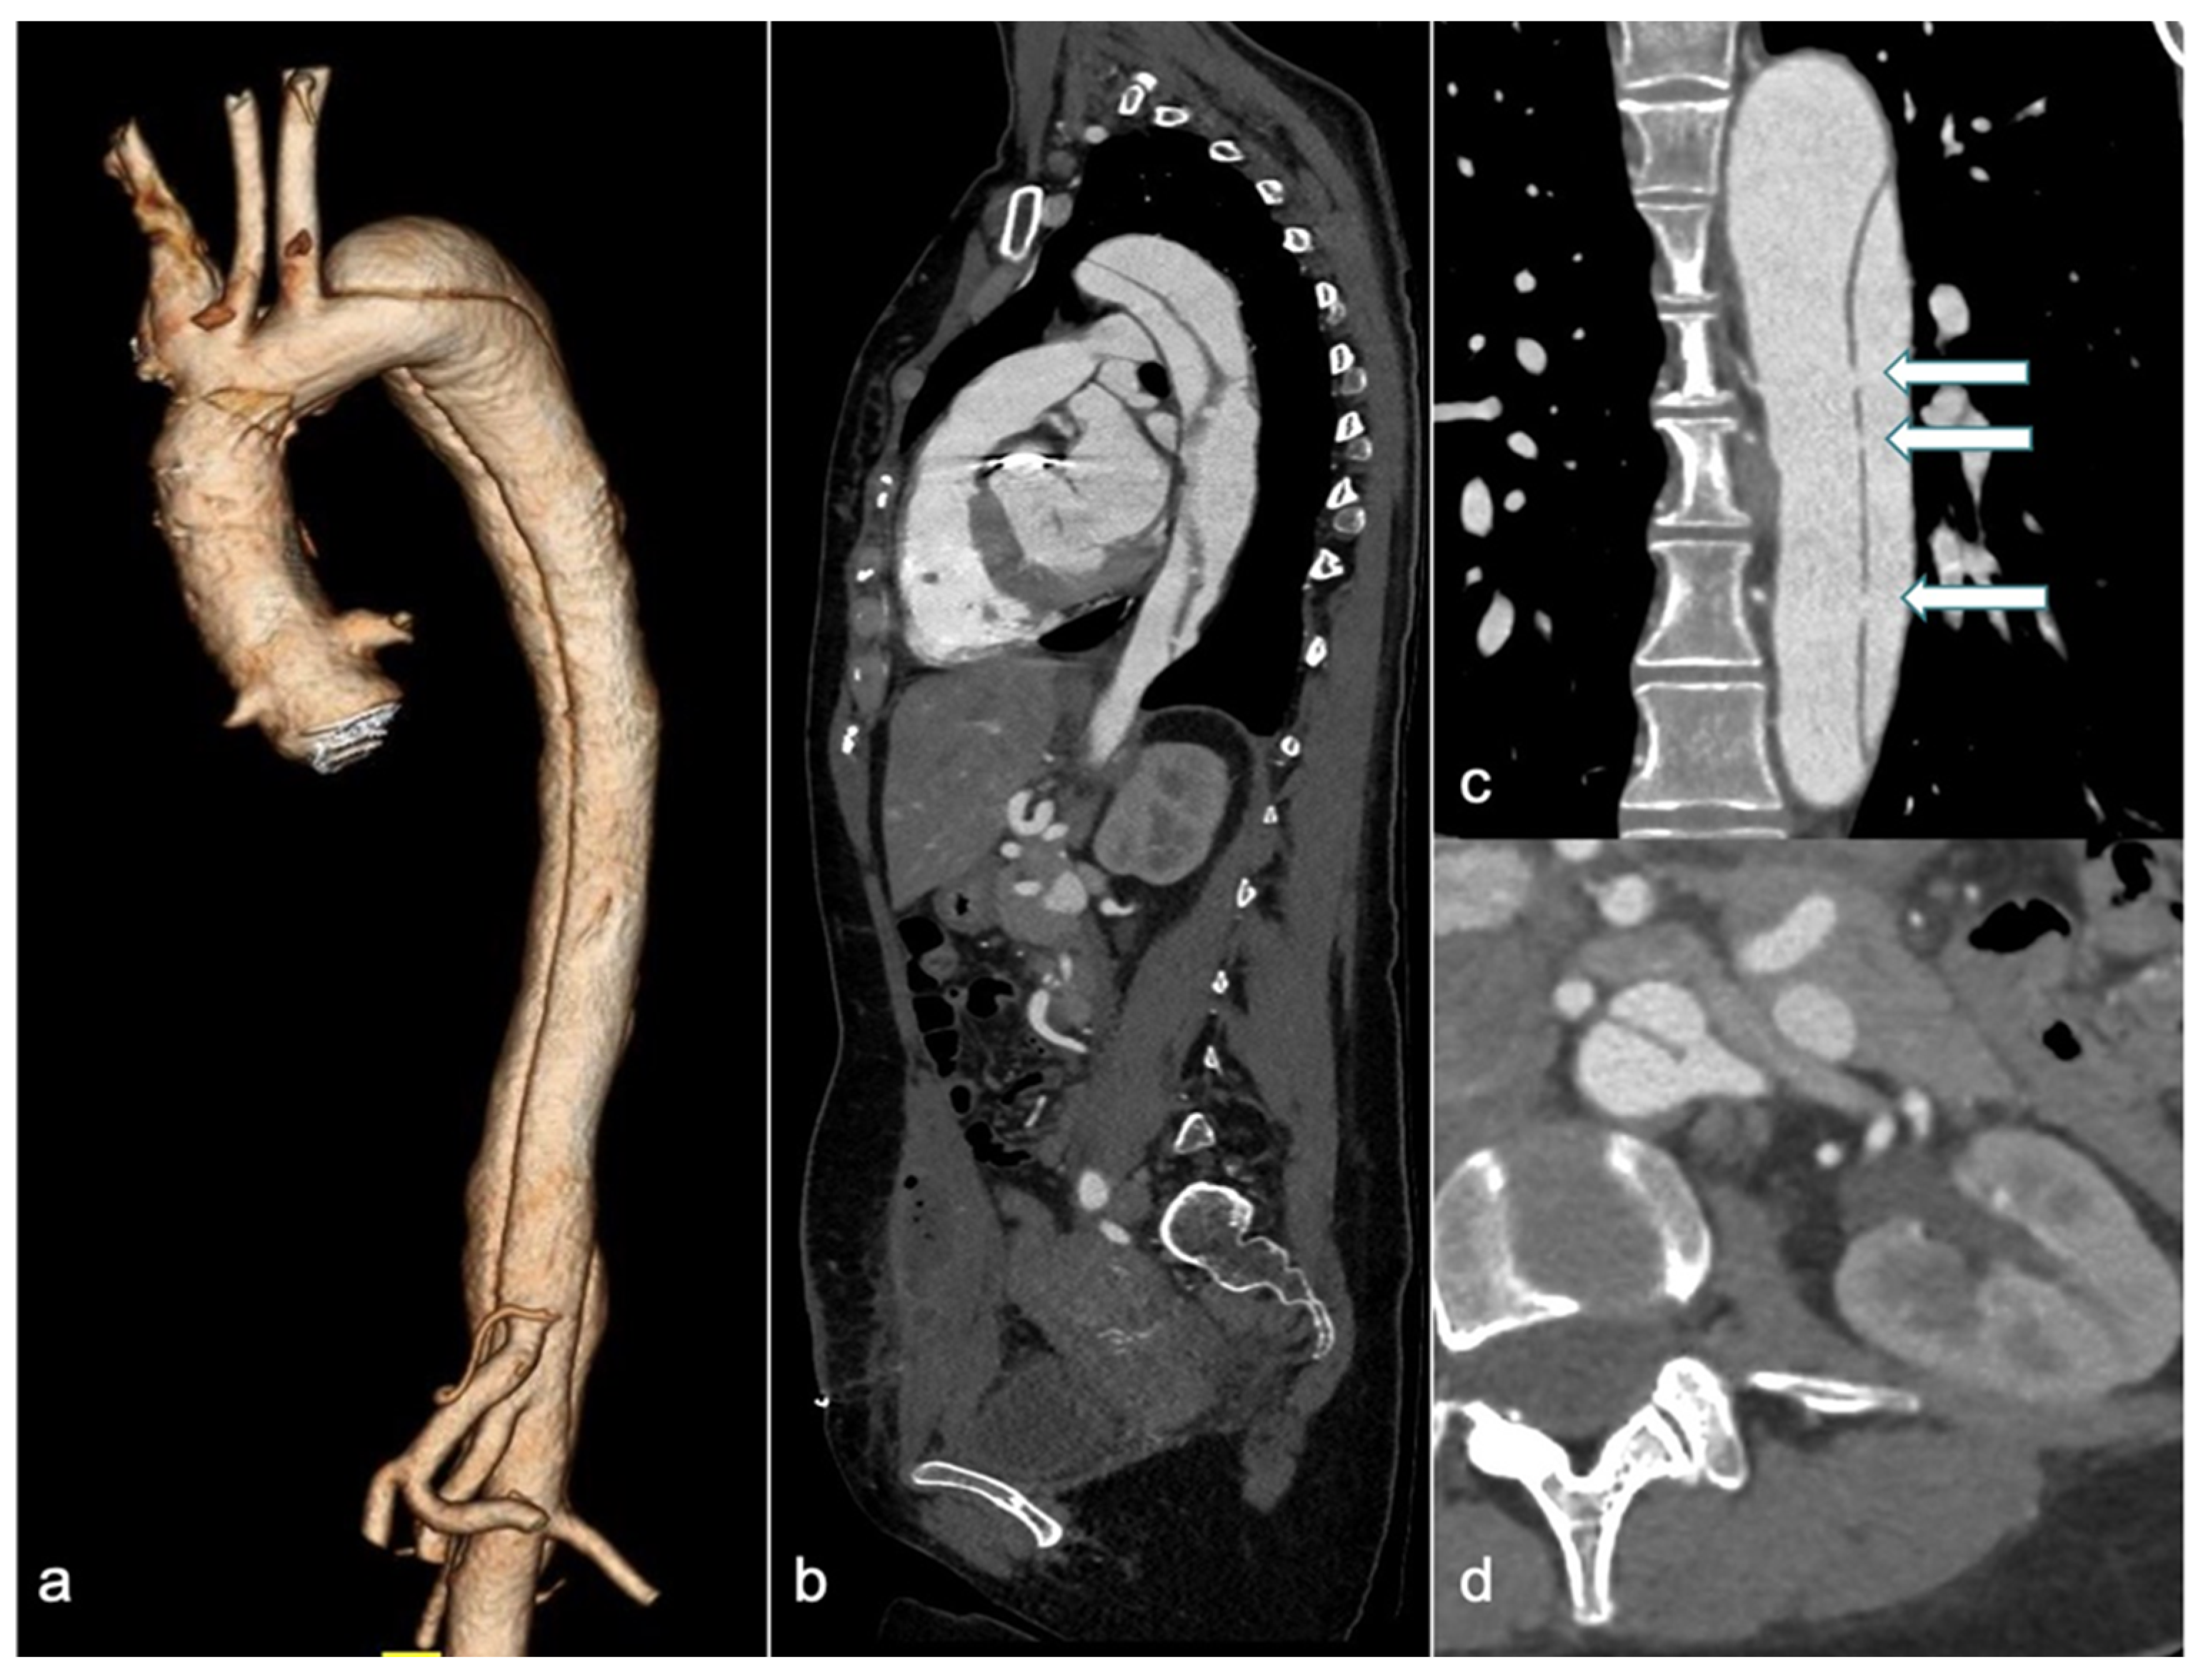

4. Aortic Dissection (AD)

4.1. CTA: Challenges and Approaches in Clinical Practice

4.2. Unenhanced MRI: When and How